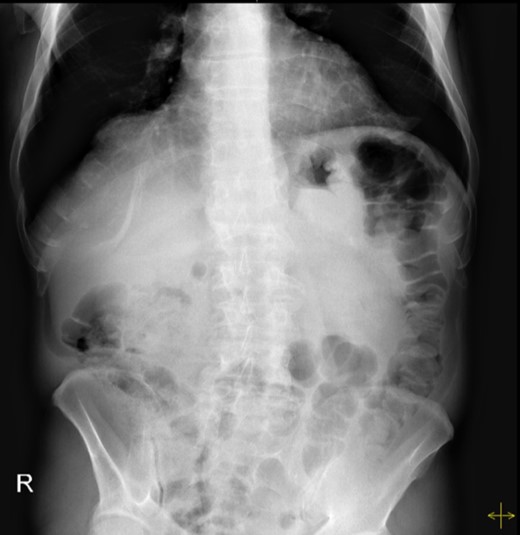

The patient’s leucocyte count and serum amylase presented mildly elevated. Chest radiograph revealed an elevated left hemi-diaphragm. Abdominal radiographs demonstrated a spherical stomach, presupposing an upward position of the pylorus (Fig. 1).

Abdominal radiograph, demonstrating a spherical stomach, presupposing an upward position of the pylorus.